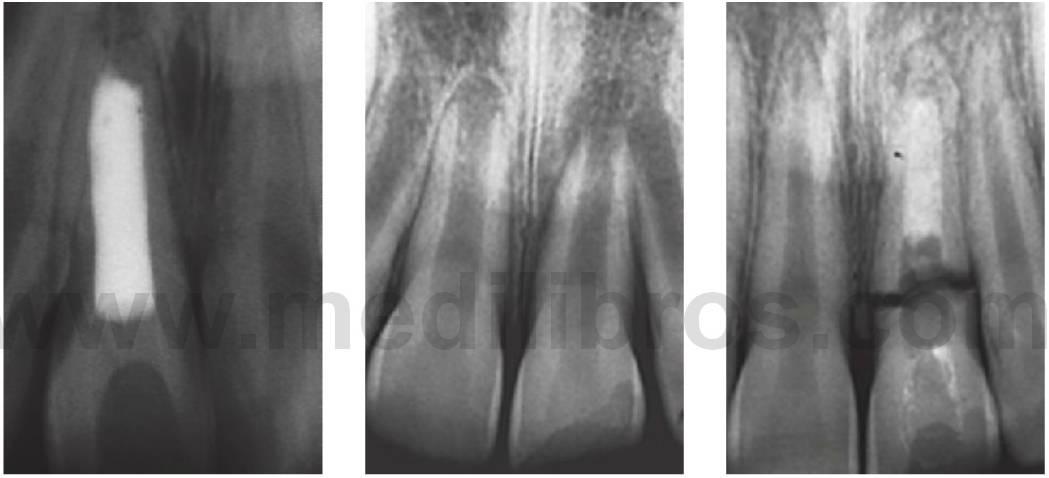

Ápice radicular incompleto con pulpa vital

Pulpectomía de Cvek (apexogénesis)

El procedimiento de pulpectomía de Cvek implica la eliminación del tejido pulpar contaminado con una fresa de diamante redonda y limpia a alta velocidad, utilizando irrigación con suero salino o agua. Un hidróxido de calcio sin fraguar se coloca directamente sobre el tejido vital no contaminado (v. paso 4 más adelante). Los pasos son los siguientes:

- Anestesia local.

- Es obligatorio el uso del dique de goma.

- La pulpa se irriga con suero salino hasta que se detiene la hemorragia. Todo coágulo se enjuagará suavemente para retirarlo.

- Se coloca el hidróxido de calcio no fraguado sobre la pulpa remanente y, posteriormente, se recubre de nuevo con un hidróxido de calcio fraguado. Se precisa imperativamente que el hidróxido de calcio se coloque sobre tejido vital y nunca sobre un coágulo sanguíneo.

- La base de cemento de ionómero de vidrio se coloca sobre los revestimientos y el diente se restaura con resina composite.

Esta técnica no necesita limitarse a la pulpa coronal y se puede realizar una «pulpotomía parcial» en cualquier zona del conducto radicular, ya que preservar la vitalidad de los incisivos traumatizados proporciona inmensos beneficios.

Revisión

- A las 6-8 semanas, y después a los 12 meses con pruebas de sensibilidad pulpar.

- Radiografías en las revisiones para comprobar la formación de la barrera de tejido duro y el desarrollo continuado de la raíz (fig. 7.22).

Pronóstico

- Tasas de éxito: 80-96%.

Se basa en la creación de una barrera de tejido duro apical (apexificación) contra el cual puede colocarse el material de obturación del conducto radicular mediante el uso de hidróxido de calcio.

Técnica (apexificación)

- Crear una cavidad de acceso con el dique de goma.

- Extirpación del tejido pulpar necrótico.

- Preparar el conducto mecánicamente 1 mm por debajo del ápice radiográfico.

- Se precisa instrumentar cuidadosamente el conducto para eliminar por completo los restos necróticos, pero preservando la mayor cantidad posible de estructura dental. La raíz apical, al ser muy fina, es débil y puede fracturarse si se ejerce una presión indebida.

- Irrigar copiosamente con hipoclorito sódico al 1 % para disolver los tejidos pulpares remanentes y desinfectar el sistema de conductos.

- Como revestimiento inicial se pondrá una pasta de mezcla de acetato de triamcinolona y demeclociclina seguida de hidróxido de calcio.

- Tras 1-2 semanas, revestir de nuevo con una pasta de hidróxido de calcio sin fraguar, mediante un obturador de pasta.

- Comprimir el hidróxido de calcio con una bolita de algodón para asegurar una buena condensación en el conducto y permitir el contacto con los tejidos apicales.

- Colocar una obturación temporal de cemento de ionómero de vidrio u óxido de zinc eugenol (material de restauración intermedio [IRM]).

Examinar al niño cada 3-6 meses. La formación de un puente calcificado puede durar hasta 18 meses, pero una vez formado el puente se puede obturar en conducto; así, el hidróxido de calcio debería cambiarse cada 2-3 meses. Este nuevo revestimiento asegurará una concentración adecuada de hidróxido de calcio y disminuirá el riesgo de infección.

La obturación se lleva a cabo con gutapercha utilizando la técnica de condensación vertical en caliente o la técnica de condensación lateral. Se puede tomar una impresión del tope apical con gutapercha reblandecida, que se cementa más adelante dentro del conducto con un sellador endodóncico. Independientemente de la técnica utilizada, es necesario aplicar una presión suave para evitar la fractura radicular o la extrusión de la barrera calcificada más allá del ápice (fig. 7.23A). A menudo, los sistemas de liberación de gutapercha termoplastificada que se utilizan en estos casos son incuestionables.